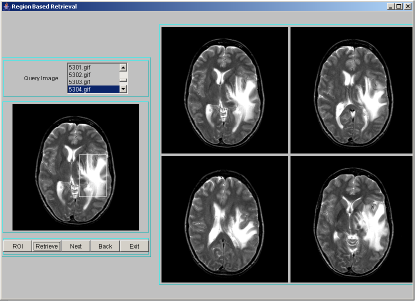

A data structure based on hashing technique is used to store all images along with the texture feature data. A combined index is adopted to point to all similar images in terms of the texture features. When a query is made based on an example image, the example image is processed for index value. Only those images that are in the same hash bucket as those of the queried image are compared for similarity. For each image in the database, segmentation procedure discussed in section 2 is applied to identify region-of-interest and describe segmented region by texture features: entropy, energy and contrast. The texture features extracted are quantized to integer values between 0 to 9. The combined index of these features is: , where [ ] represents quantization. Each combined index stores feature data along with the image object. For a query image, after finding the region-of-interest, the above mentioned texture features have to be computed, quantized and the combined index derived. Only those images that are stored at the combined index matching those of the query index, are extracted as resultant target images for a given query image. These resultant images are sorted using Euclidean distance measure in the decreasing order of similarity against the query image and displayed four images at a time using JAVA-AWT based GUI. A few representative snapshots of region-based indexing and retrieval are shown in Figure 1. Hash table offers very fast insertion and searching. Irrespective of the size of the data, insertion and searching can take close to constant time . Not only are they fast, hash tables are simple and easy to implement. Searching using hash tables are significantly faster than using tree, which operate in time.

|

|